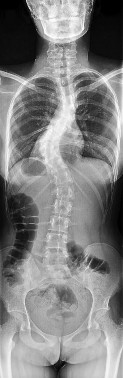

A newborn is diagnosed with congenital scoliosis secondary to a fully segmented hemivertebra at T8.

A newborn is evaluated for congenital scoliosis. Which of the following radiographic vertebral anomalies carries the highest risk for rapid, unrelenting curve progression and typically requires early in situ spinal fusion?